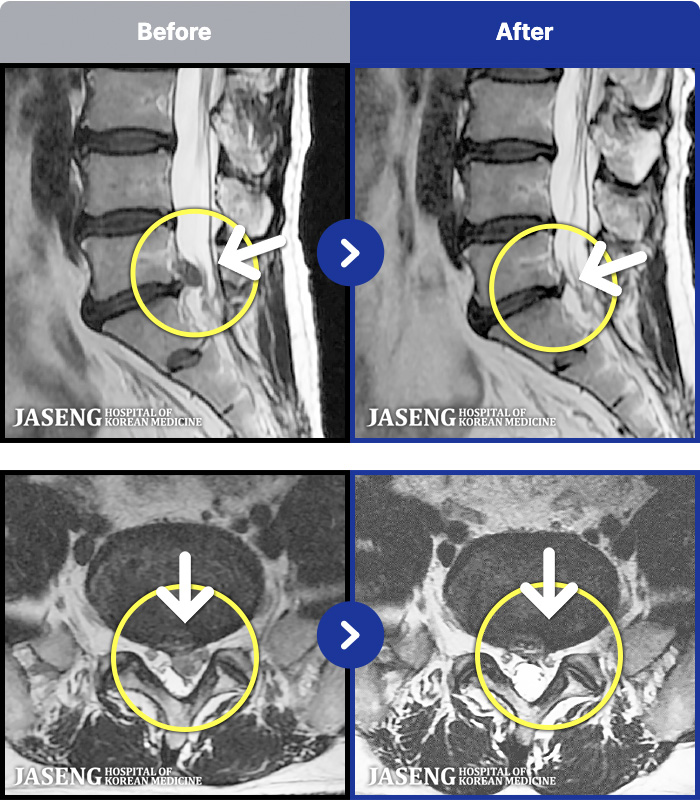

- MRI ġ

MRI ġ

1,304 MRI ũ ʸ Ȯϼ.